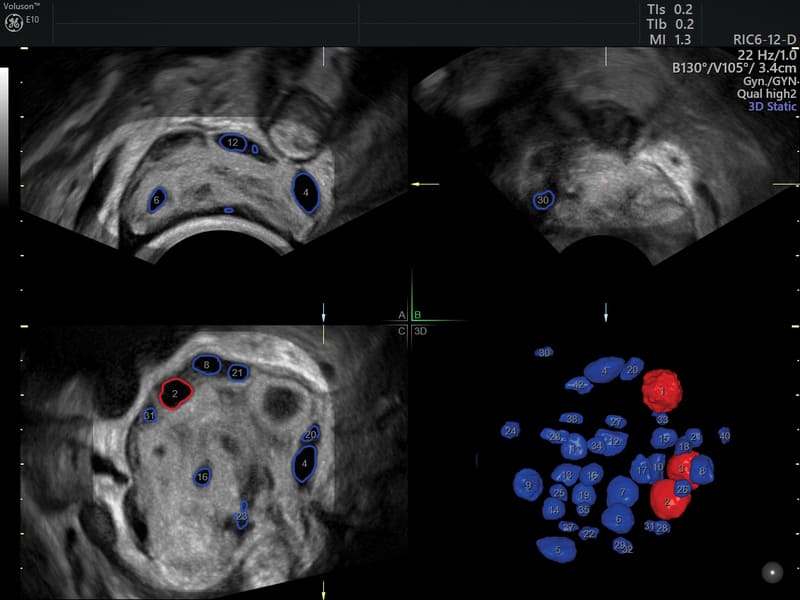

SonoAVC Follicle, Antral e General (Sonography Based Automated Volume Count Analysis): strumento avanzato, basato sulla tecnologia Volume Ultrasound con AI inside, che permette il riconoscimento automatico, semiautomatico ed interattivo dei follicoli